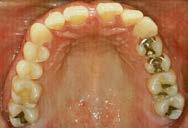

Estudio de caso

El paciente se presentó después de varios años de sufrir una herida traumática en sus dientes anterio res superiores. Las piezas 11 y 21 tenían varias fracturas, así como el borde incisal de la pieza 12. Por lo que él deseaba mejorar su estética bucal, y yo quería asegurarme de restaurar la funcionalidad y resisten cia también. El paciente necesitaba completar su tratamiento en un cor to periodo de tiempo, por ello debí realizar ajustes en mi flujo de traba jo. (Figura 1).

Cita 1. Impresiones iniciales y planeación del tratamiento

Mi plan era restaurar los dientes 12-22 con carillas BruxZir® Esthe tic, así que tomé un escaneo digital de ambas arcadas completas, ade más del registro de mordida usan do el escáner iTero® Element (Align Technology; San Jose, Calif.). Puede tomar impresiones de vinil polisiloxa no (VPS) si lo prefiere, pero el esca neo digital reduce tiempos al eliminar la necesidad de enviar modelos físicos o impresiones al laboratorio. Envío dicho escaneo junto con instruccio nes específicas para que Glidewell fabrique un encerado de diagnóstico (Figura 2).